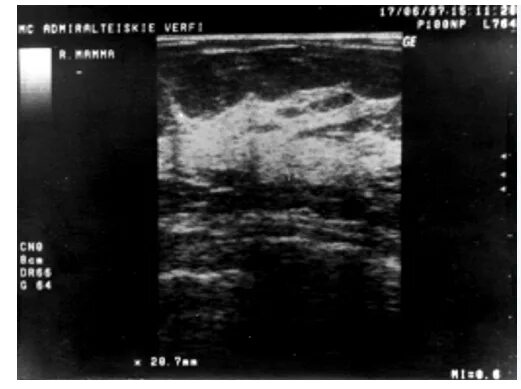

Линейный фиброз молочных желез